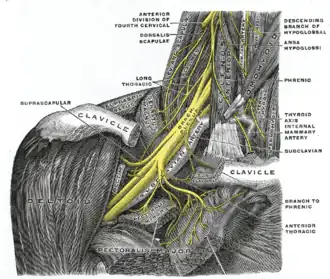

- Arm pains Muscular spasms within the arm are further common symptoms in which such spasms are seen right above the collarbones and pressure is placed on the Brachial plexus causing arms to feel heavy and ache.[1]